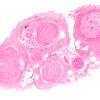

3A1 Sarcoid (Case 3) H&E 1